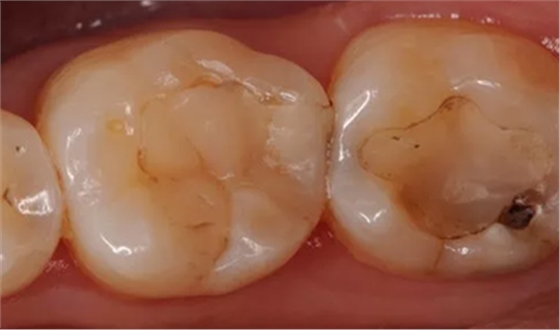

如 PPT22 圖示下為臨床治療常見(jiàn)的邊緣白線,造成了充填體邊緣的不密合,圖上是治療的時(shí)腐質(zhì)沒(méi)有去除干凈,繼續(xù)發(fā)展以后出現(xiàn)摸尋狀的改變。